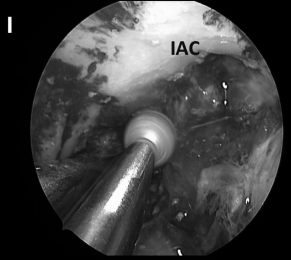

▼(I)s使用磨钻去除该区域粘附于岩骨的病变包膜,但切除岩骨深处病变的增强部分考虑是不顺利的,因为它与内听神经关系密切。

▼(J)使用Endocameleon内镜仔细检查术野、鼻道(IAC)

神经内镜手术“动态控制”的重要关键优势是,它允许外科医生逐步靠近目标并放大术野,同时减少鼻腔内手术器械操作之间的冲突。这在某些情况下如重要神经组织的解剖分离、肿瘤暴露中至关重要的,例如在颈内动脉附近钻孔、暴露视神经顶部或在硬膜内分离解剖过程中。此过程类似于在执行更细致的操作时使用显微镜进行放大。例如,在手术操作系列图中,我们可以了解当从骨质解剖分离颈内动脉ICA(A)、从硬脑膜上解剖病变包膜(D)或耳蜗下的骨质时,神经内镜与磨钻头的距离有多近(I)。该技术结合了耳鼻喉科和神经外科手势的优点。